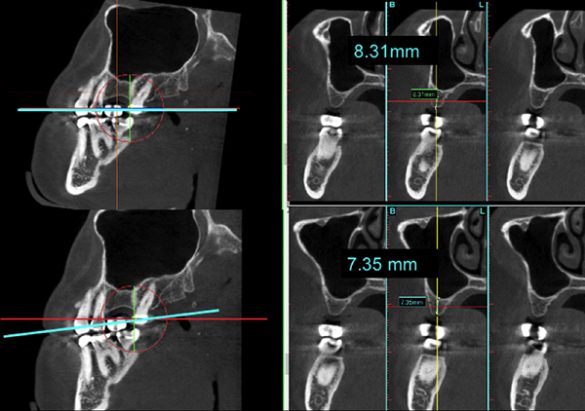

Măsurătorile din scanarea CBCT au fost înregistrate pe secțiunea transversală. O linie dreaptă perpendiculară pe o tangentă la creastă a fost extinsă până la podeaua sinusului maxilar. S-a măsurat lungimea liniei și s-a notat ca „înălțimea crestei CBCT” (fig. 1, 2). Măsurătorile periapicale ale aceleiași zone au fost înregistrate prin extinderea unei linii drepte paralele cu axul lung al dintelui natural sau implantului adiacent, de la creasta alveolară până la podeaua sinusului maxilar. Lungimea liniei a fost măsurată și înregistrată ca „înălțimea crestei PA” (fig. 3).

De asemenea, orientarea setărilor planului de referință au un impact asupra măsurătorilor liniare.18 Acest lucru poate fi vizualizat în fig. 10, care prezintă un exemplu pentru diferite măsurători liniare obținute cu o setare a planului de referință cu +/- 12°. În prezentul studiu, s-a verificat setarea planului de referință, pentru a avea linia secțiunii transversale paralelă cu dintele adiacent, așa cum se vede în fig. 1-3.